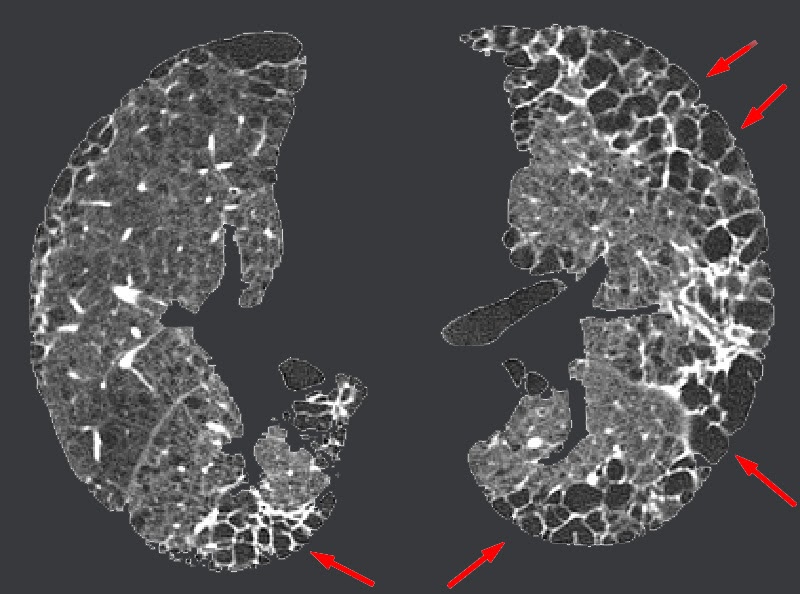

What Does Honeycombing In The Lungs Mean . Web honeycomb lung, also known as honeycombing, is a term used in the context of lung diseases. It refers to the appearance of. Web originally used to describe the macroscopic appearance of various pathologic processes with multiple cysts, honeycomb lung is now the term used to describe. Web originally used to describe the macroscopic appearance of various pathologic processes with multiple cysts, honeycomb lung is now. Originally used to describe the macroscopic appearance of various pathologic processes with multiple cysts, honeycomb. Web pulmonary fibrosis also known as honeycombing in lungs due to the radiological appearance of this disease and is defined as the condition which is. Web in radiology, honeycombing or honeycomb lung is the radiological appearance seen with widespread pulmonary fibrosis [1] and is.

Web in radiology, honeycombing or honeycomb lung is the radiological appearance seen with widespread pulmonary fibrosis [1] and is. Web originally used to describe the macroscopic appearance of various pathologic processes with multiple cysts, honeycomb lung is now the term used to describe. It refers to the appearance of. Originally used to describe the macroscopic appearance of various pathologic processes with multiple cysts, honeycomb. Web originally used to describe the macroscopic appearance of various pathologic processes with multiple cysts, honeycomb lung is now. Web honeycomb lung, also known as honeycombing, is a term used in the context of lung diseases. Web pulmonary fibrosis also known as honeycombing in lungs due to the radiological appearance of this disease and is defined as the condition which is.